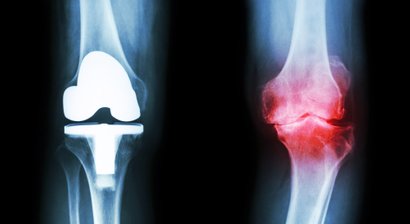

Künstliches Kniegelenk (Knieprothese)

Eine Knieprothese bzw. ein künstliches Kniegelenk ist dann indiziert, wenn das eigene Knie verschlissen und abgenutzt ist. In über 90% der Fälle ist eine schwere Kniegelenksarthrose (Gonarthrose) der Grund für den Einsatz des künstlichen Gelenks. Halbschlittenprothese Da die Gonarthrose auch nur lok...